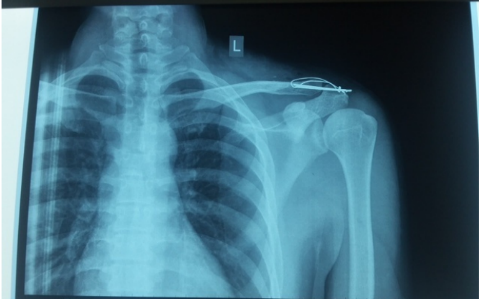

Hình ảnh kết hợp xương khớp cùng đòn bằng đinh và chỉ thép